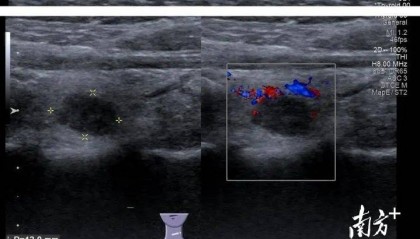

小罗是一名在校女大学生,家住在吉林省白城市,近期体检中发现甲状腺有个结节,彩超提示为C-TIRADS...